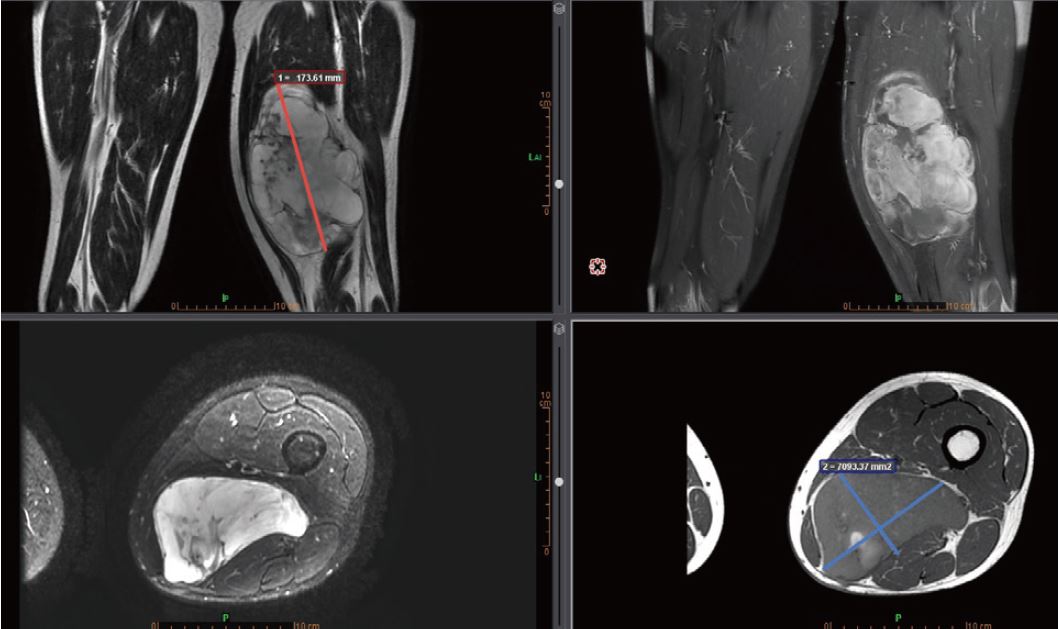

Multi-Modality Viewer полегшує морфологічний огляд (рис. 2), що є важливим кроком в оцінці саркоми м’яких тканин. Для моніторингу цих пухлин доступні вимірювальні або об’ємні інструменти, зокрема з використанням критеріїв відповіді пухлини «RECIST 1.1».

Рисунок 2